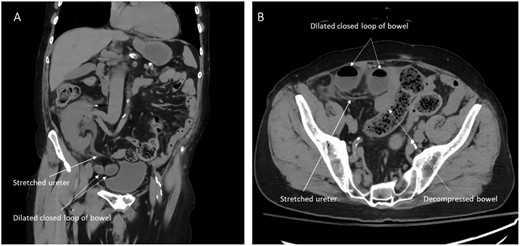

A 73 year-old man with history of end-stage renal disease secondary to reflux uropathy underwent living donor renal transplantation 23 years prior. The transplant was performed via a right Gibson incision. Review of the medical records indicated the kidney was placed intraperitoneal as the peritoneum was adherent to the abdominal wall from prior right native nephrectomy. The patient underwent multiple subsequent surgeries: right inguinal hernia repair, sigmoidectomy with diverting loop ileostomy and ileostomy reversal. A previous bout of SBO was managed conservatively and resolved with nasogastric tube decompression and intravenous hydration. He presented to the emergency department with signs and symptoms of SBO. Laboratory values were normal except for creatinine of 1.7 mg/dL from a baseline of ˂1.0 mg/dL. A non-contrast computed tomography (CT) demonstrated closed loop SBO and new hydronephrosis of his transplanted kidney (Fig. 1). A nasogastric tube was placed, and the patient was taken to the operating room where multiple non-obstructive adhesions were noted on diagnostic laparoscopy. A congested loop of small bowel was found herniated under the intraperitoneal transplanted ureter causing the ‘double obstruction’ of the bowel and the ureter. Laparoscopic reduction of the loop was unsuccessful thus a laparotomy was undertaken. The bowel loop was reduced, and viability was confirmed clinically and via administration of indocyanine green dye. No resection was required.

CT images showing herniated ileal loops under the transplanted ureter. (A) Coronal view. (B) Axial view.